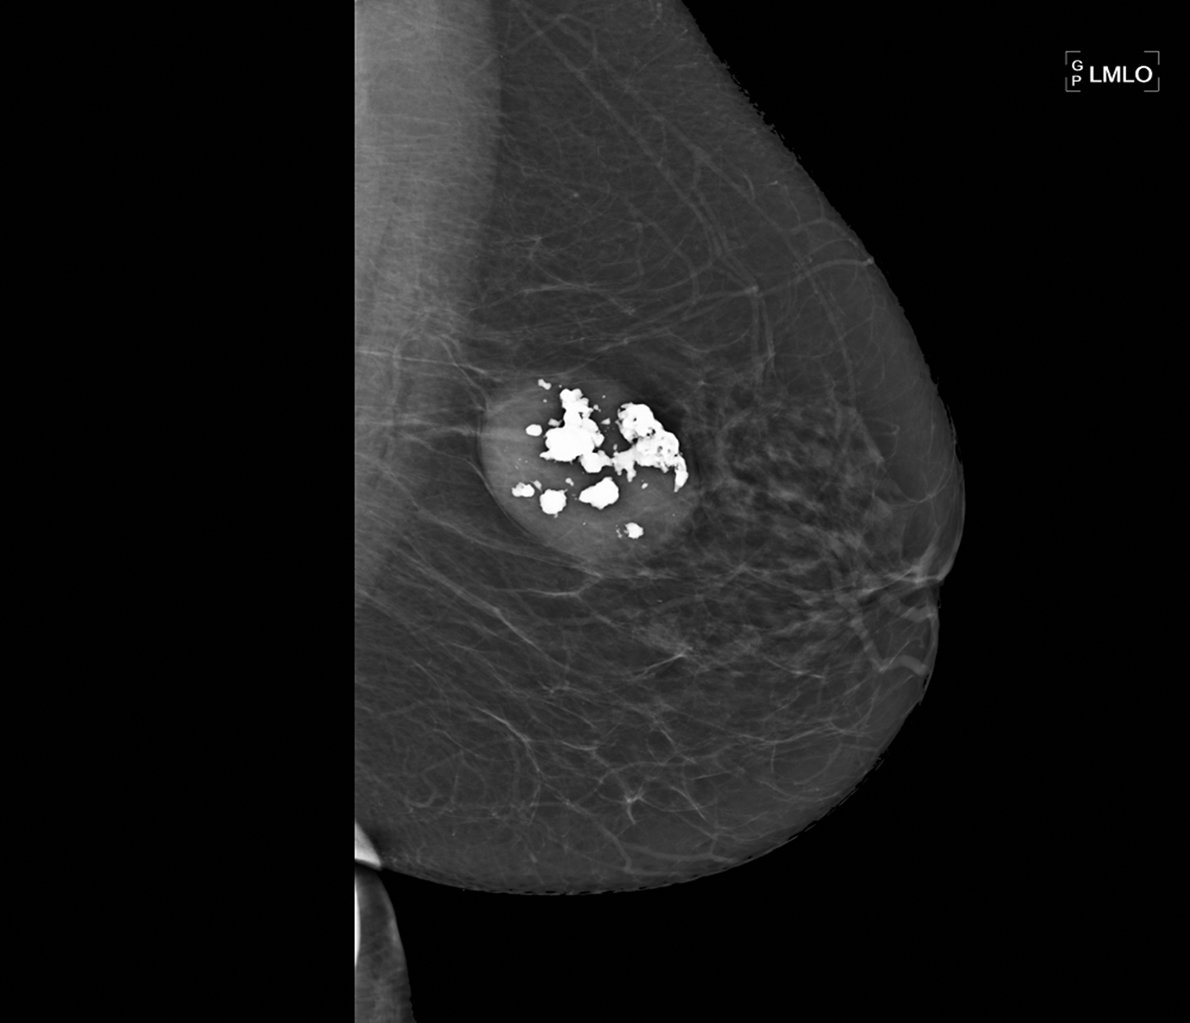

Figure 20.5 Aspect mammographique d’un fibroadénome : image à contours réguliers avec présence de macrocalcifications.